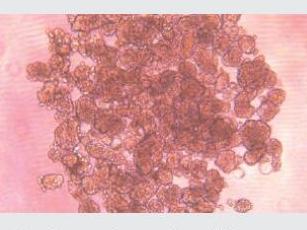

與傳統(tǒng)的2D培養(yǎng)模型相比,3D球體模型能夠更好的模擬三維細(xì)胞網(wǎng)絡(luò)、細(xì)胞與基質(zhì)、細(xì)胞與細(xì)胞之間的相互作用,因此,對藥物篩選、體外腫瘤研究和干細(xì)胞分化與分選等的探索有著重要意義。

潔特生物3DSphearo™超低吸附表面產(chǎn)品設(shè)計(jì)用于擬球體(如 3D 腫瘤細(xì)胞球)和類器官培養(yǎng),提供培養(yǎng)板、培養(yǎng)皿和培養(yǎng)瓶等多種產(chǎn)品形式。產(chǎn)品表面經(jīng)特殊凝膠處理后,具有極強(qiáng)的抗蛋白吸附性和抗細(xì)胞貼壁性,表面幾乎無細(xì)胞貼壁,利于細(xì)胞的懸浮生長,可快速實(shí)現(xiàn)可重復(fù)、一致的細(xì)胞球體培養(yǎng)。

經(jīng)不同細(xì)胞培養(yǎng)測試驗(yàn)證,表面幾乎無細(xì)胞貼壁,可快速實(shí)現(xiàn)可重復(fù)、一致、可靠的細(xì)胞球培養(yǎng)

*經(jīng)不同細(xì)胞培養(yǎng)測試驗(yàn)證,表面幾乎無細(xì)胞貼壁,可快速實(shí)現(xiàn)可重復(fù)、一致、可靠的細(xì)胞球培養(yǎng)